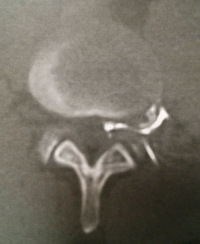

Hernie Discale

Coupe scanner

Le disque est normalement très solide et riche en eau mais son usure naturelle est inévitable par déshydratation (dès l’âge de 30 ans) expliquant sa diminution de hauteur avec l'âge. Cette dégénérescence ne provoque le plus souvent aucune douleur.

Cette « involution » du disque est parfois émaillée de complications. Au cours de la dégénérescence discale (également appelée discopathie), le disque va souvent présenter un simple bombement à sa partie postérieure, c'est la protusion discale, qui peut se traduire par des lombalgies plus ou moins aiguës, parfois des sensations de blocage lombaire (lumbago).

Tandis que le nucleus se fragmente, l'annulus se fendille et permet à des fragments de nucléus de migrer vers l'arrière du disque. On parle alord de hernie discale. Cette hernie ne génère pas réellement de douleurs lombaires (bas du dos), mais va occasionner une douleur dans la jambe (sciatique) par compression des racines nerveuses formant le nerf sciatique.